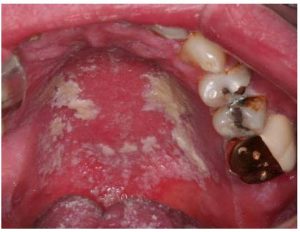

Amalgam Ve Kandidiyazis Candida

Fotoğrafların ortak yönü : amalgam-kandidiyazis

Kapsamlı klinik deneyimlerden, kanserin yayılmasının genellikle mantar / Candida insidansı ile ilişkili olduğu bulunmuştur ve Candida’yı kan alkalinite dengesi ve toksik metal vücut seviyesinde azalma yoluyla tedavi etmenin kanserin yayılmasını azalttığı bulunmuştur. Bu tür tedaviler ayrıca hücrelere oksijen tedarikini de arttırır.